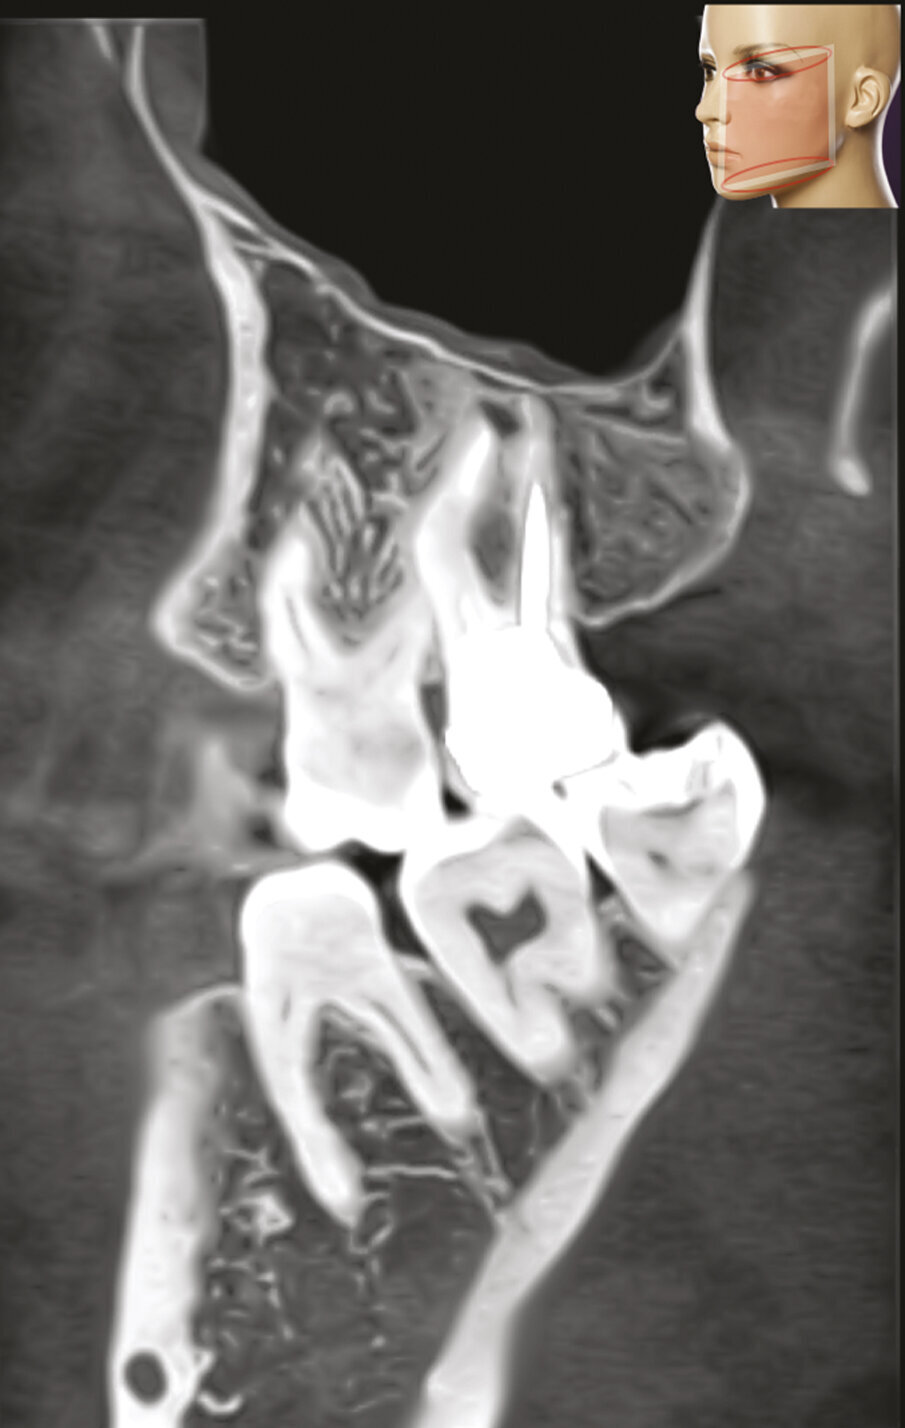

Fig. 1a - Il paziente è stato inviato per la terapia chirurgica della radice mesiovestibolare del primo molare superiore di destra.

Fig. 1b - Una radiografia presa con diversa angolazione sembra confermare che l’unica radice coinvolta nella lesione periapicale è la mesiovestibolare.

Fig. 1c - La CBCT mostra il riassorbimento dell’osso corticale adiacente la radice distovestibolare.

Figg. 1d, 1e - Un’altra lesione periapicale sta interessando il secondo molare.

Fig. 1f, 1g - La sezione sagittale mostra ancora meglio le lesioni a carico del primo molare su entrambe le radici vestibolari e le lesioni a carico di entrambe le radici vestibolari del secondo molare, il cui canale MB1 appare completamente vuoto.

Fig. 1h - La sezione assiale mostra le lesioni del primo e del secondo molare, interessanti queste ultime per l’aspetto palatino delle due radici. È ovvio il motivo per cui tali lesioni non erano apprezzabili nella radiografia periapicale.